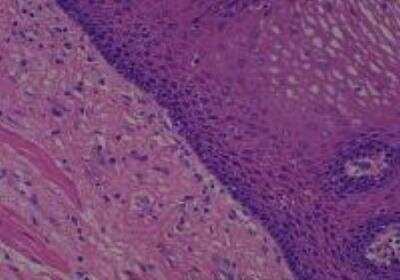

Hematoxylin & Eosin Stain: Human Common Tissue MicroArray (Normal Adjacent) [NBP2-30215] - 103. Stomach